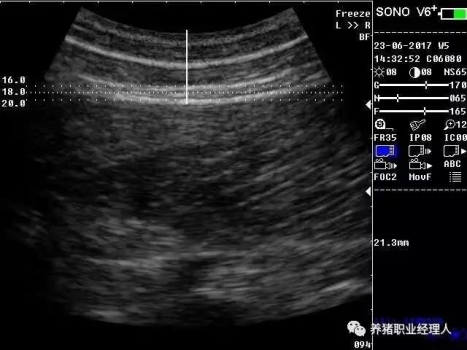

根據(jù)以上表格,活體測膘與實體測膘的相關(guān)分析及活體膘厚與胴體瘦肉率的相關(guān)分析結(jié)果證明,最后肋骨處和腰薦結(jié)合處離背中線5cm處(B5、C5)可作為活體測膘的最佳部位。 根據(jù)中華人民共和國農(nóng)業(yè)行業(yè)標(biāo)準(zhǔn)(NY/822-2004)種豬生產(chǎn)性能測定規(guī)程規(guī)定:生產(chǎn)性能背膘值運(yùn)用A超儀器測量的需測定腰薦椎結(jié)合處(P1)、胸腰椎結(jié)合處(P2)距背中線左側(cè)5cm處,兩點(diǎn)背膘厚平均值。生產(chǎn)性能背膘值運(yùn)用B超儀器測量的需測定倒數(shù)第三和第四肋骨間距背中線左側(cè)5cm處背膘厚。 2.3 剔剪剪毛 因為超聲波是不能在空氣中傳播的,所以在利用儀器測量之前,先用剔剪剪去測定部位的豬毛,方便測量儀器探頭與豬皮膚的無縫接觸。剪毛面積一般為5cm×5cm左右。此時若皮膚死皮結(jié)痂較多,便可用溫水擦洗去痂。 2.4涂耦合劑 耦合劑是檢測儀探頭與豬皮膚之間的中間潤滑劑,作為超聲波從儀器發(fā)出到豬體表和從豬體表回到儀器的傳播介質(zhì)。所以耦合劑的作用是排除探頭與豬體表之間的空氣和作為超聲波傳播的介質(zhì)。它是準(zhǔn)確測定背膘所不能缺少的。 2.5 正確測量 因為豬體表脂肪分為三層。所以不管是用A超還是B超,我們一般都能同時測量到三個數(shù)值,而正確反映豬只體況的是第三個數(shù)值。如圖所示:

測量時,盡量讓豬只安靜,避免豬只弓背或塌腰而使測量數(shù)據(jù)出現(xiàn)偏差。探頭應(yīng)直線平面與豬背正中線縱軸面垂直,不可斜切。同時探頭應(yīng)與豬背密接且不重壓。 2.6 讀取記錄數(shù)據(jù) 若為A超,讀取儀器亮三個指示燈時的數(shù)值,記錄下來。若為B超,觀察并調(diào)節(jié)屏幕影響,獲得理想影像時即凍結(jié)影像,測量背膘厚和眼肌面積,并加以說明標(biāo)記。影響打印或保存處理。 3、通過背膘測定指導(dǎo)豬生產(chǎn)飼喂管理 以妊娠母豬為例: 表3 妊娠母豬適宜背膘值范圍